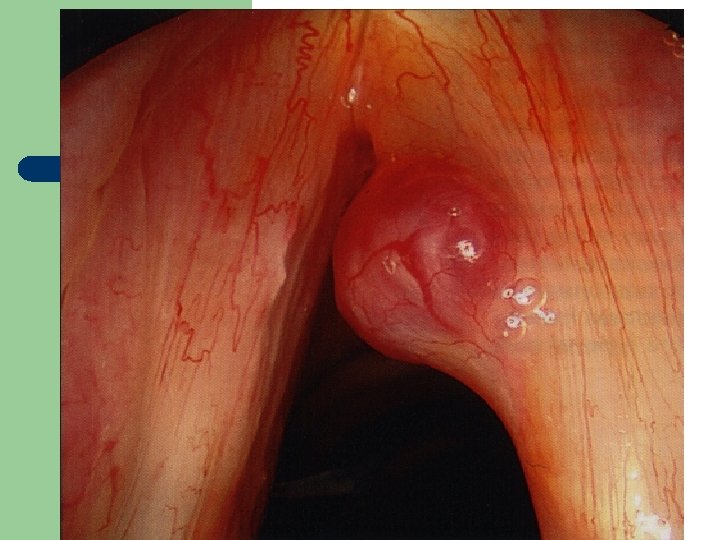

Hlasivkový uzlík l

Hlasivkový uzlík l

Hlasivkové uzlíky l